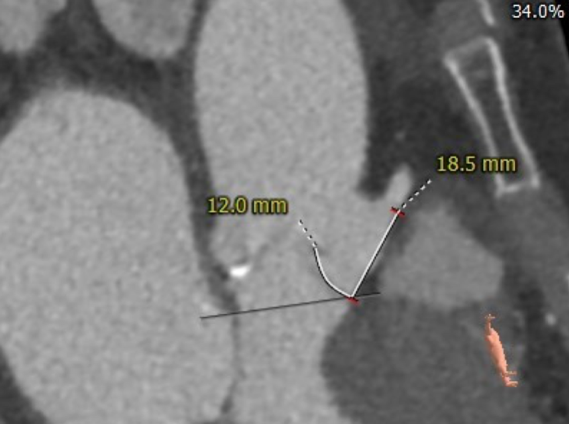

主动脉根部评估

CT 数据显示该患者为三叶式主动脉瓣